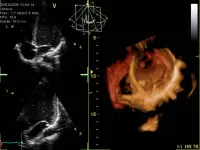

Le malattie cardiovascolari fanno parte del gruppo delle malattie cronico-degenerative che nei paesi occidentali si contendono il primato della mortalità con il cancro.

La presentazione di questa pagina parte dalla definizione di ischemia, per analizzare poi l'aterosclerosi, la sua nascita e progressione, l'epidemiologia e i fattori di rischio. L'aterosclerosi è quindi una vera e propria malattia cronico-degenerativa che ha i suoi bersagli principalmente nell'arteria aorta, nelle coronarie e nelle arterie cerebrali.

Giocoforza quindi valutarne, nella parte finale della presentazione, le conseguenze, soprattutto l'infarto del miocardio.